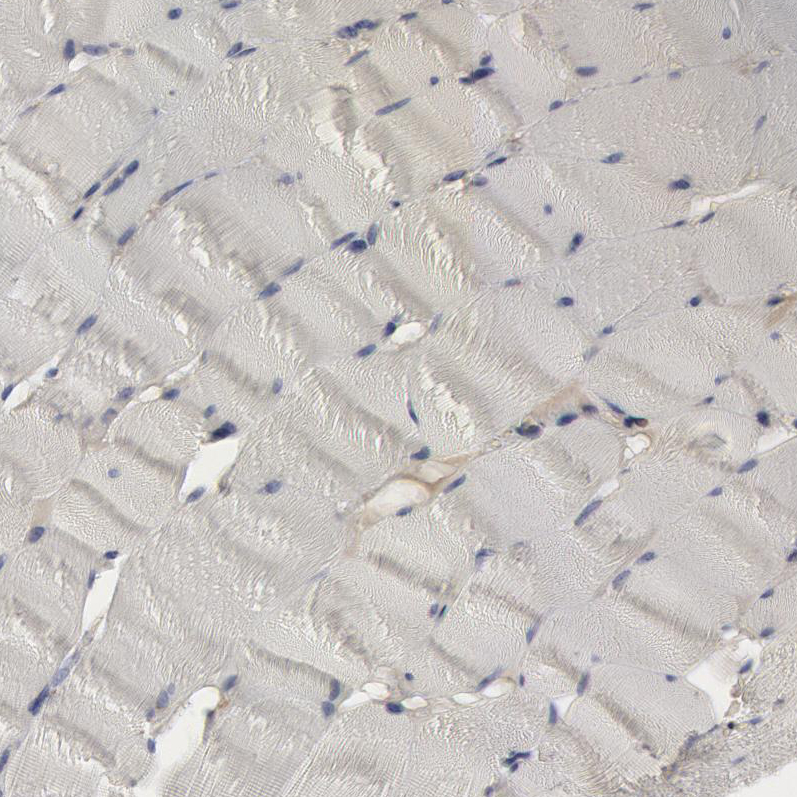

Immunohistochemical staining of human spleen shows strong cytoplasmic positivity in cells in red pulp.